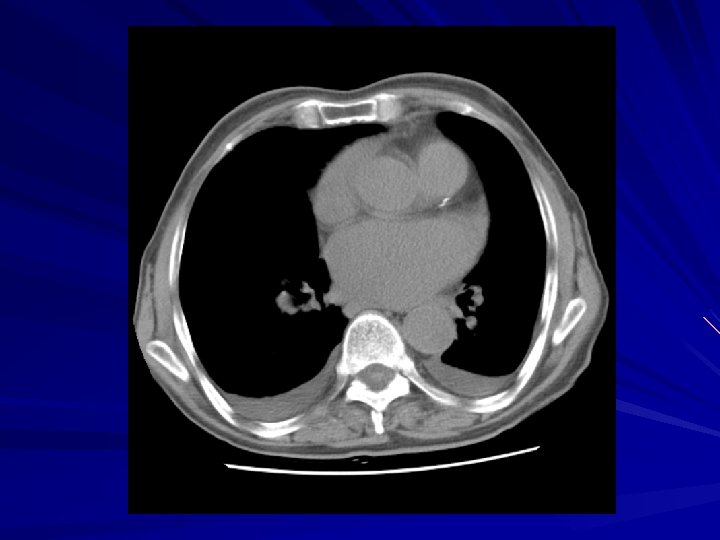

Plevral efüzyonda BT Çok duyarlı: minimal effüzyonlar saptanır Loküle effüzyonların saptanması Effüzyon – konsolidasyon ayrımı Ampiyem – apse ayrımı Nedeni ortaya koyabilir (pnömoni, malignansi, kalp yetmezliği, …) Benign – malign plevral hastalık ayrımı – %70 -80 doğruluk